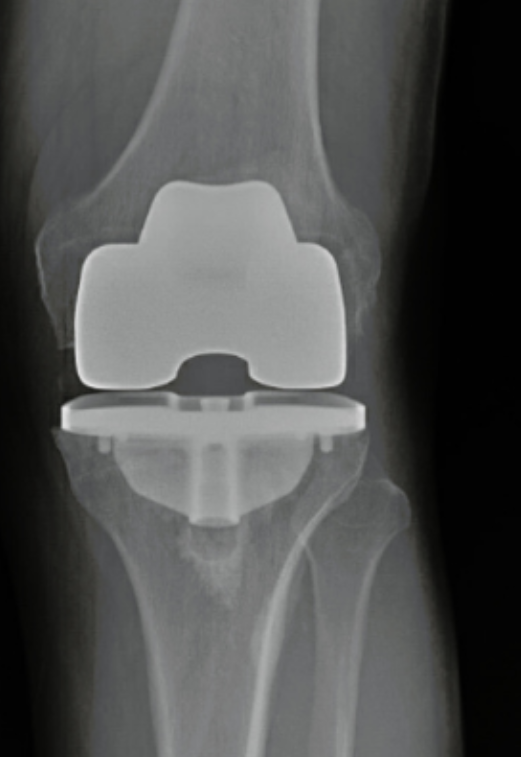

Total Joint Orthopedics makes high-quality, efficient implants for hip and knee replacement. Our streamlined instrumentation is intuitive and easy to use for reproducible results.